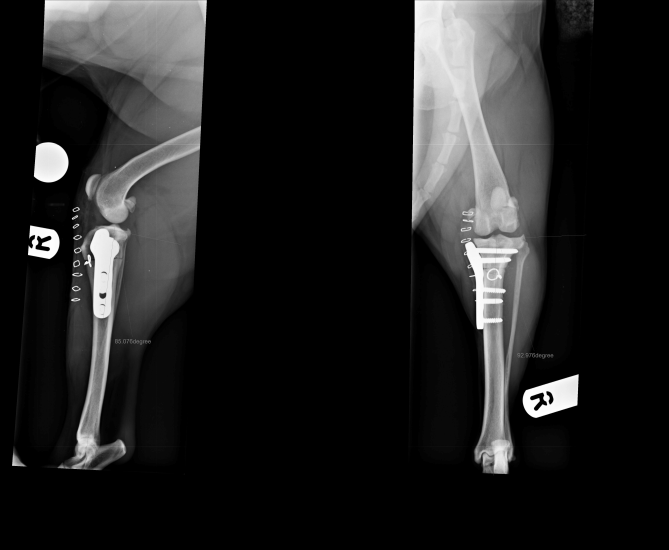

CCWO achieves tibial plateau levelling in a different way to TPLO but will have similar biomechanical effects. We use CCWO for dogs with proximal tibial deformity leading to angulation between the proximal and distal tibial axes. This includes many small breed dogs with cranial cruciate ligament disease. It is an effective way to treat cranial cruciate ligament disease in juvenile dogs where implants cannot be placed across the open physes, allowing unimpeded continued growth of the tibia (Figure 2).

Figure 2. Treatment of cranial cruciate ligament rupture in a West Highland white terrier using a cranial closing wedge ostectomy stabilised with a locking plate and screws